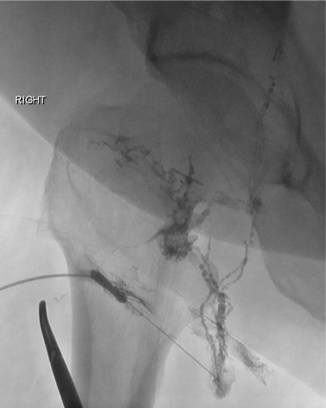

M/47, 结直肠外科术后(腹主动脉旁淋巴结清扫)Chylous ascites after surgery for rectosigmoid cancer (with para-aortic lymphadenectomy)

1:6 mixture of NBCA: Lipiodol

7 months later